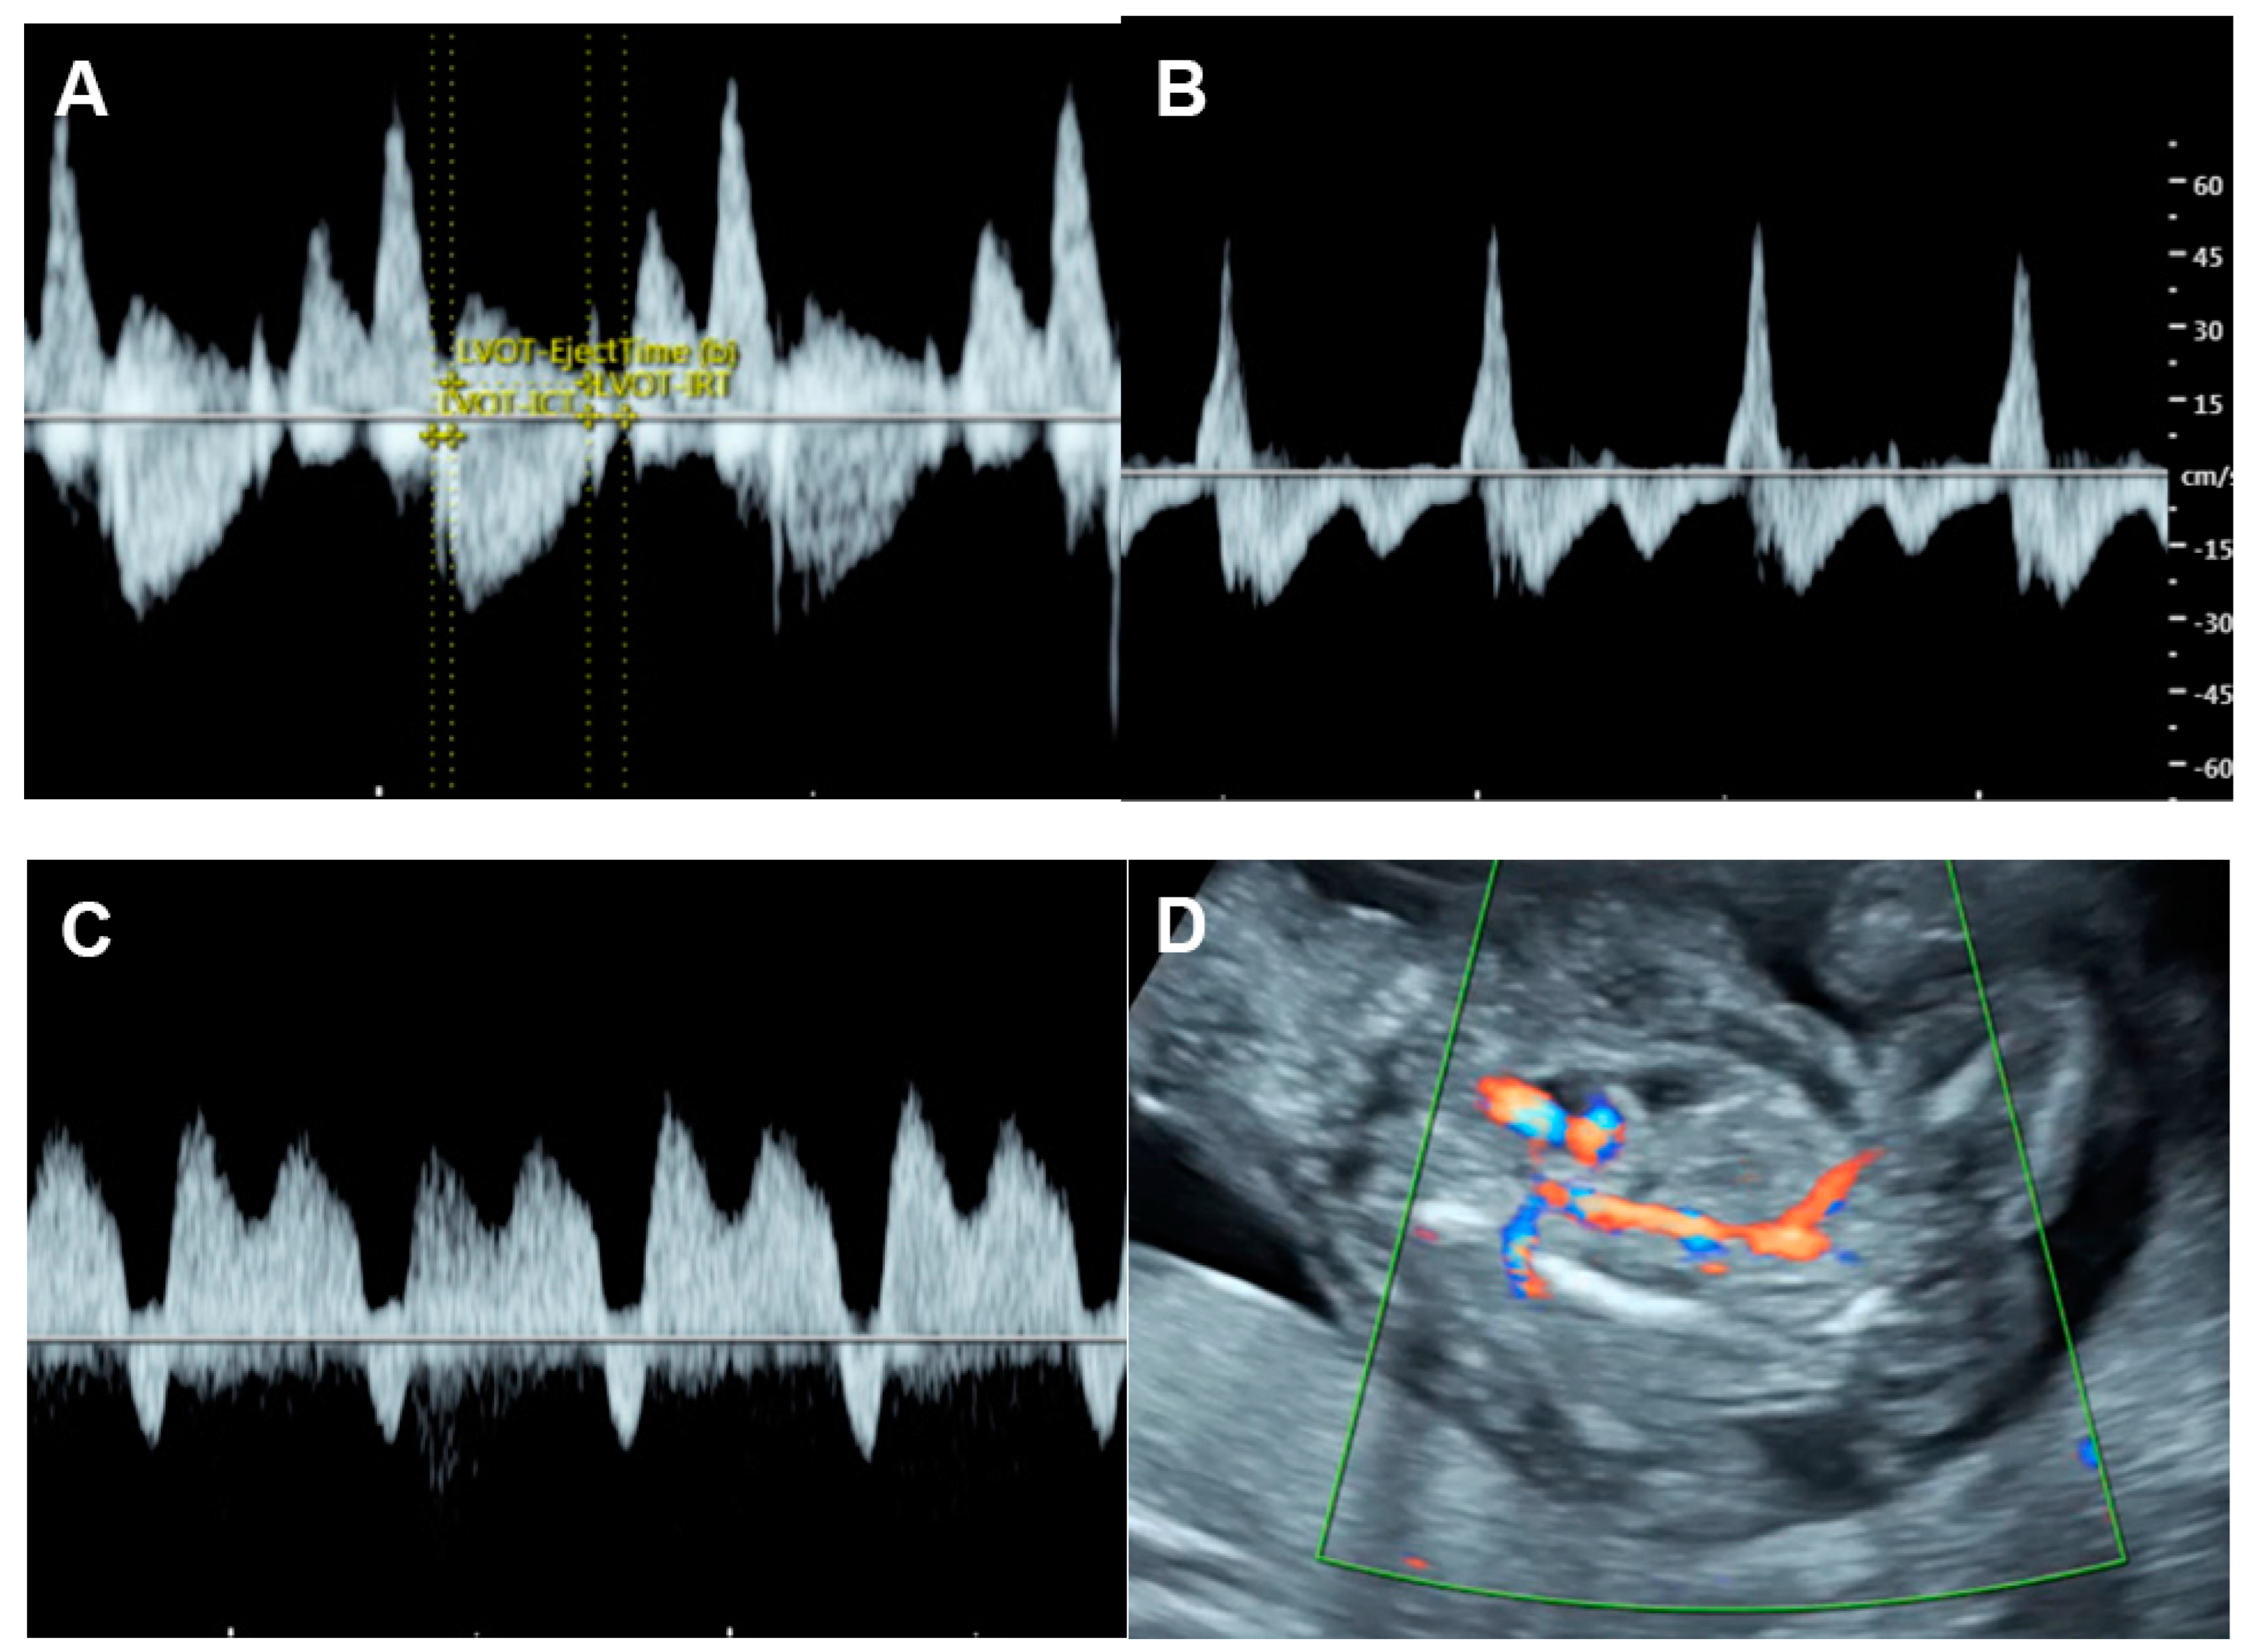

| Parameters | Abnormal Changes | Interpretation |

| Inflow characteristics | ||

| Filling time fraction | Decreased | Diastolic dysfunction |

| E/A ratio | Monophasic | Diastolic dysfunction |

| Decreased | Diastolic dysfunction | |

| Increased | Volume loading/External compression | |

| Performance | ||

| Shortening fraction | Decreased (<28%) | Systolic dysfunction |

| Increased | Reduced afterload/increased contractility | |

| Ejection fraction | Decreased <50%) | Systolic dysfunction |

| Cardiac output (Stroke volume) | Decreased (Z < −2) | Systolic dysfunction/poor filling |

| Increased (Z > +2) | Reduced afterload/volume load | |

| Tei index | Increased > 0.50 | Global cardiac dysfunction |

| ICT: 28 (22–33) ms | Prolonged | Systolic dysfunction |

| IRT: 34 (26-41) ms | Prolonged | Diastolic dysfunction |

| Systolic strain/Strain rate | Increased | Reduced afterload |

| Decreased | Reduced contractility | |

| E/Vp (Color M-mode) | Increased | Diastolic dysfunction |